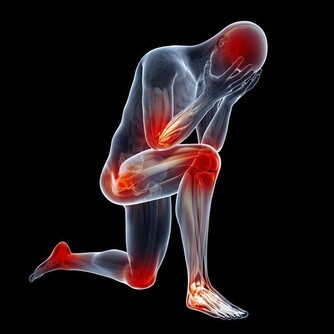

這個時候,很多患者就會使用嘴部張口呼吸,出現睡覺打呼嚕的症狀。而長期張口呼吸會使上下頜咬合關係發生變化,導致兒童上下頜發育不良,可能出現面部拉長、嘴唇增厚症狀,直接影響面容。

過敏性鼻炎的發作還會影響病人消化系統。王主任解釋,門診很多患有過敏性鼻炎的小朋友都會比較矮瘦,就是因為鼻炎影響到了生長發育,所以一般通過治療改善了以後,小孩的食慾都會有明顯改善,從而消除生長發育因鼻炎受到抑制的問題。